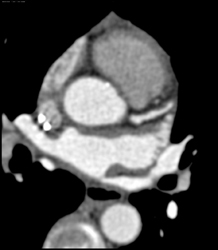

CASE NUMBER 685

Normal LAD and Circumflex Artery (CX)